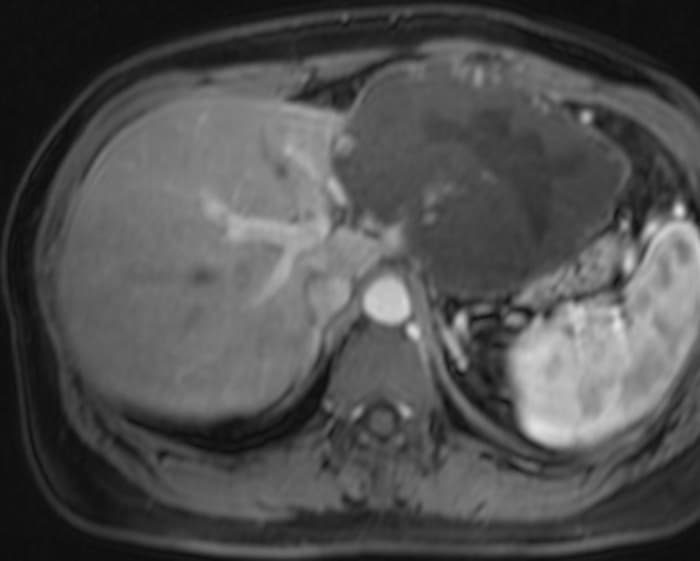

U máu gan

» Thông tin: Nữ giới – 47 tuổi.

» Lâm sàng: Đau thượng vị.